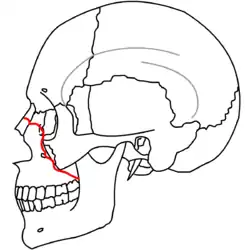

|

|

| Le Fort I fractures | |

At the beginning of the 20th century, René Le Fort mapped typical locations for facial fractures; these are now known as Le Fort I, II, and III fractures (right).[7] Le Fort I fractures, also called Guérin or horizontal maxillary fractures,[14] involve the maxilla, separating it from the palate.[15] Le Fort II fractures, also called pyramidal fractures of the maxilla,[16] cross the nasal bones and the orbital rim.[15] Le Fort III fractures, also called craniofacial disjunction and transverse facial fractures,[17] cross the front of the maxilla and involve the lacrimal bone, the lamina papyracea, and the orbital floor, and often involve the ethmoid bone,[15] are the most serious.[18] Le Fort fractures, which account for 10–20% of facial fractures, are often associated with other serious injuries.[15] Le Fort made his classifications based on work with cadaver skulls, and the classification system has been criticized as imprecise and simplistic since most midface fractures involve a combination of Le Fort fractures.[15] Although most facial fractures do not follow the patterns described by Le Fort precisely, the system is still used to categorize injuries.[5]